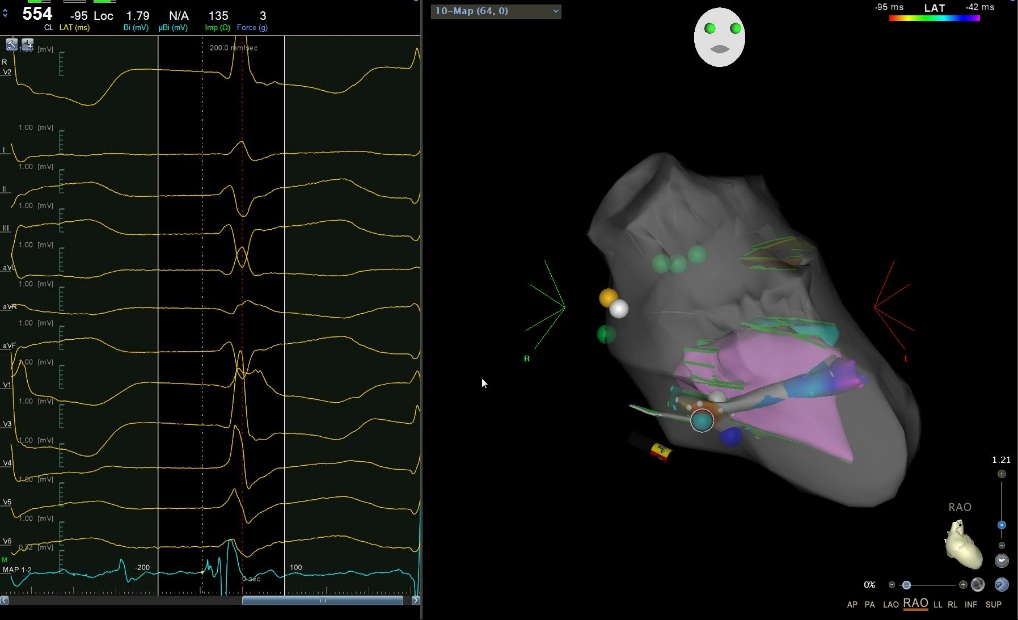

51岁女性患者,因胸闷、心悸半月于2022年5月28日入院,行动态心电图检查提示频发室早,室早负荷超过20%,于是来我院寻求治疗。根据患者心电图室早形态判断,室早可能来源于左后乳头肌,于是术者结合了心腔内超声进行室早消融手术。术中标测发现室早来源于左后乳头肌前组和后组之间,使用压力导管贴靠乳头肌就如同走钢丝,导管难以稳定贴靠,最终在心腔内超声指导下在两组乳头肌之间寻找到最佳靶点和稳定贴靠方式消融成功。

左后乳头肌超声建模和压力导管贴靠消融